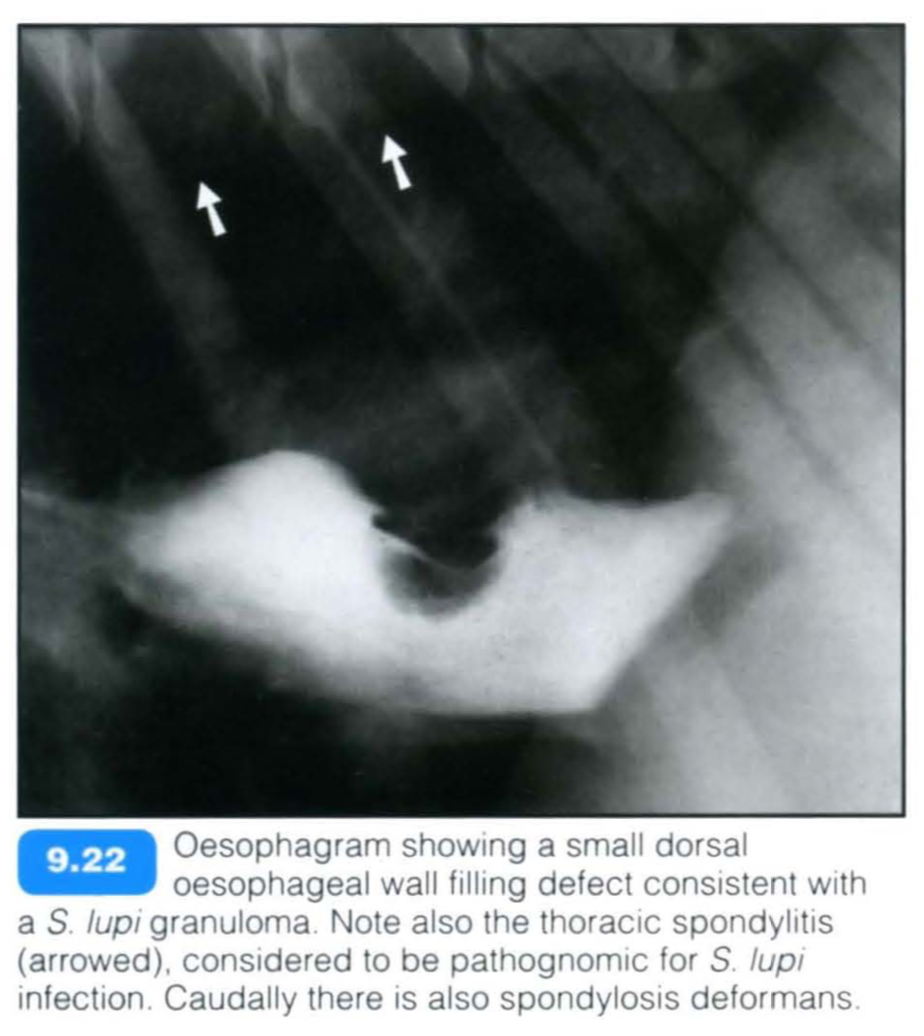

The nematode Spirocerca lupi may lead to the development of oesophageal granulomas and neoplasms. The condition is common in endemic areas (most tropical and subtropical countries) but otherwise very rare. Although any breed can be affected , the condition is seen more commonly in large-breed dogs. Infections in cats are seldom reported.

Eggs containing first-stage infective larvae are eaten by coprophagous dung beetles. Dogs then ingest the beetle or a paratenic host and the larvae penetrate the gastric wall, migrate through arteries and finally reach the thoracic aorta in about 3 weeks. After 10-12 weeks in the aorta the larvae migrate to the oesophagus and it is here that the adult develops within nodules in the oesophageal wall. With time, a granuloma forms and is typically situated in the terminal oesophageal wall. In atypical cases, it may be hilar and smaller. Granulomas may undergo neoplastic transformation to fibrosarcomas/osteosarcomas in 26-41 % of cases. Animals typically present with regurgitation (or less commonly vomiting) or an oesophageal mass may be identified as an incidental finding.

Complications can occur due to perforation of the oesophagus (mediastinitis, pleuritis, mediastinal haematoma, aberrant migration with abscess formation) or rupture of the aortic aneurysm (acute haemothorax) . Parotid salivary gland hypertrophy with hypersalivation may also occur.

Radiographic findings include:

Contrast studies: